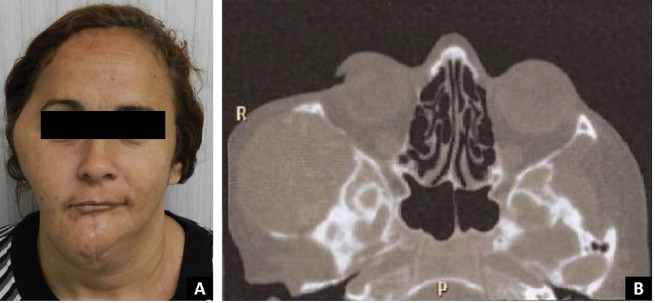

The term keratoameloblastoma has been used to describe a histologically heterogeneous group of ameloblastoma variants that share the formation of keratin by the ameloblastomatous epithelium. To date, thirty-eight cases of keratoameloblastoma have been previously reported in the literature, nine of which exhibited a papilliferous component. Here we report a new case of a recurrent tumor that falls within the keratoameloblastoma spectrum. It presented as an expansile, solid lesion with internal calcification in the right infratemporal fossa six years after ipsilateral hemimandibulectomy in a 46-year-old white female. Histological evaluation revealed islands of columnar cells resembling ameloblasts surrounding a central area with stellate reticulum-like cells, some of them completely filled with keratin. In addition, areas showed basal ranging from columnar to cuboidal with hyperchromatic nuclei. The clinical, histopathologic, and radiographic features of keratoameloblastoma are reviewed, along with treatment approaches and follow-up considerations. Although only a few cases have been documented, the tumor's aggressive biological behavior and the high recurrence rate suggest that a more aggressive therapeutic approach is warranted. Patients should be informed of the importance of clinical monitoring. Surgical resection with adequate safety margins and histopathological evaluation of the margins is strongly recommended. Key words:Odontogenic tumors, keratoameloblastoma, ameloblastoma, review.